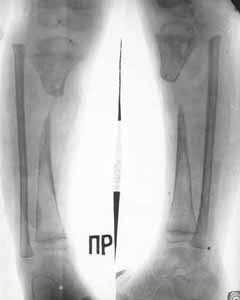

| Replacement phase of the defect by means of Ilizorov's apparatus. |